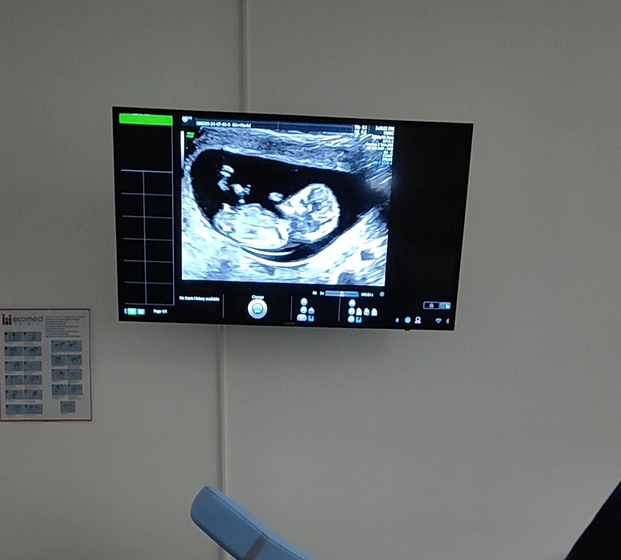

Первый скрининг.

Все хорошо, но не понравилось что-то с верхней губой, попросили приехать на 15-16 неделе и повторить УЗИ.

Срок по УЗИ — 12,1 неделя.

Фото прилагаю